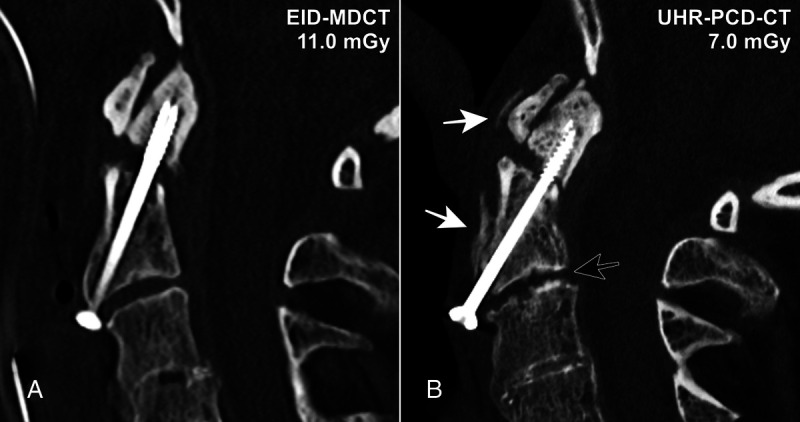

摘要:光子计数探测器(PCD)是近年来医学成像领域最具影响力的技术发展之一。PCD-CT 扫描仪在许多方面都超越了采用能量集成探测器技术的传统系统,可为所有放射亚专科提供卓越的空间分辨率和剂量效率。肌肉骨骼(MSK)成像需要在同一次扫描中详细显示骨小梁微结构和广泛的解剖学覆盖范围,因此 PCD-CT 的卓越性能尤其使其受益匪浅。然而,由于 PCD-CT 为用户提供了大量图像采集和重建的定制选项,因此 MSK 放射科医生需要熟悉该扫描仪,才能充分挖掘其潜力。从基于滤波器的光谱整形以减少全视野超高分辨率扫描的伪影,到单源或双源多能数据的后处理,几乎所有成像任务都可以通过 PCD-CT 的优化方法来完成。本综述旨在概述迄今为止 PCD-CT 在 MSK 成像中最有前景的应用,说明目前的局限性,并强调未来研究和发展的方向。

Abstract: Photon-counting detectors (PCDs) have emerged as one of the most influential technical developments for medical imaging in recent memory. Surpassing conventional systems with energy-integrating detector technology in many aspects, PCD-CT scanners provide superior spatial resolution and dose efficiency for all radiological subspecialities. Demanding detailed display of trabecular microarchitecture and extensive anatomical coverage frequently within the same scan, musculoskeletal (MSK) imaging in particular can be a beneficiary of PCD-CT's remarkable performance. Since PCD-CT provides users with a plethora of customization options for both image acquisition and reconstruction, however, MSK radiologists need to be familiar with the scanner to unlock its full potential. From filter-based spectral shaping for artifact reduction over full field-of-view ultra-high-resolution scans to postprocessing of single- or dual-source multienergy data, almost every imaging task can be met with an optimized approach in PCD-CT. The objectives of this review were to give an overview of the most promising applications of PCD-CT in MSK imaging to date, to state current limitations, and to highlight directions for future research and developments.